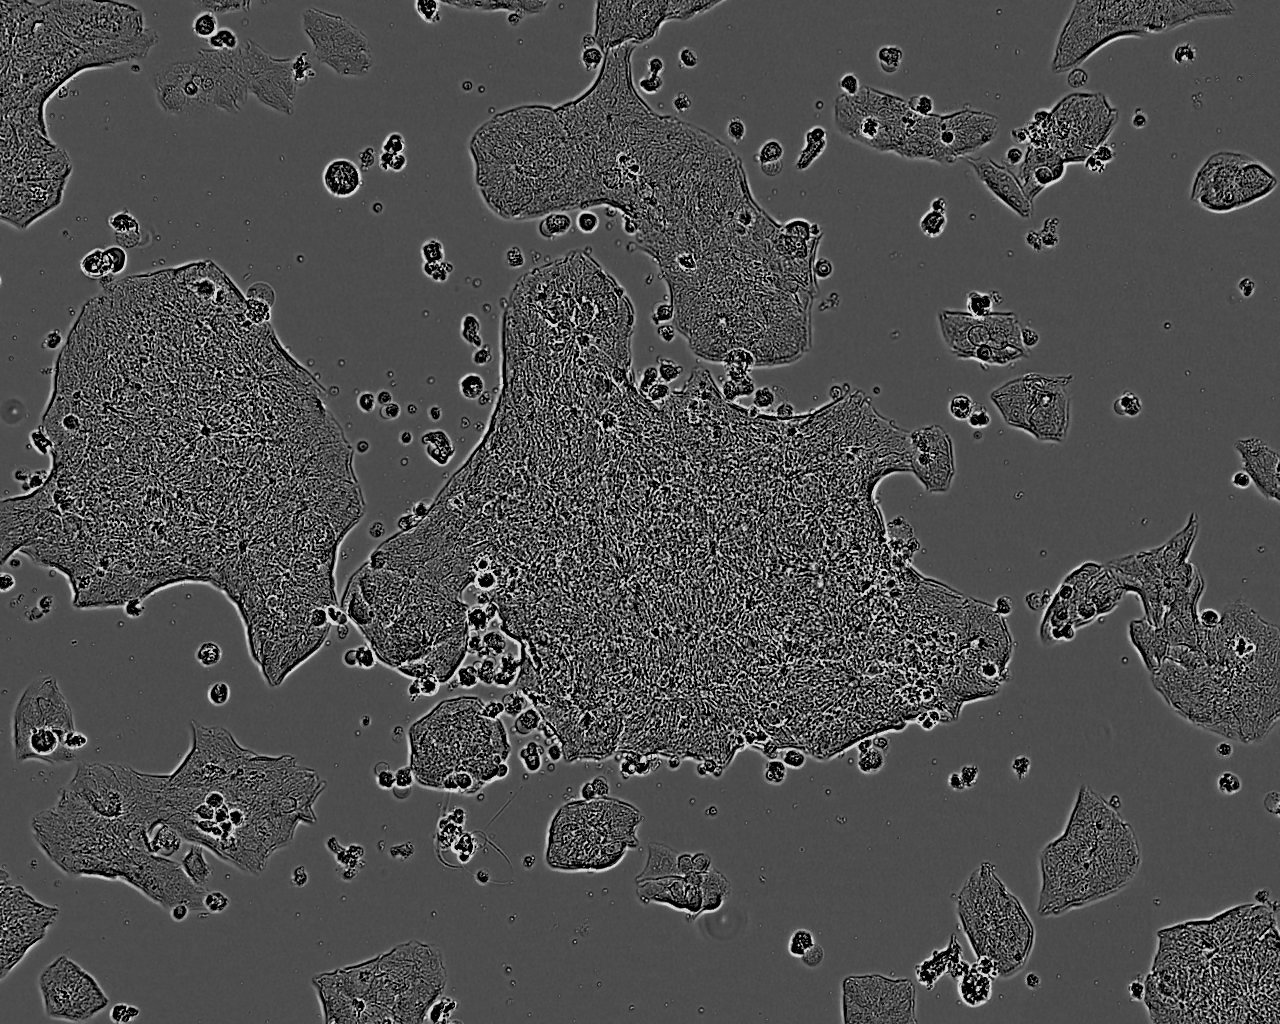

细胞生长:贴壁

细胞背景资料:该细胞1982年由T.C. Hamilton等建系,源自一位60卵巢腺癌的腹水,是卵巢癌抗药性研究的模型。

细胞形态:上皮细胞样

细胞生长特性:贴壁生长